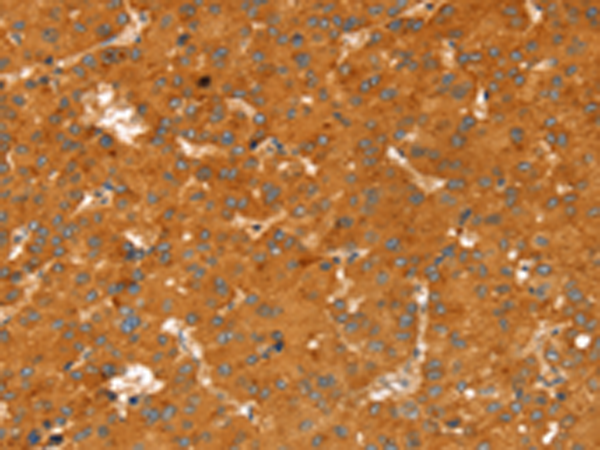

分类: 科研抗体货号: P08700别名: RNASE6PL; bA514O12.3应用: IHC反应种属: Human